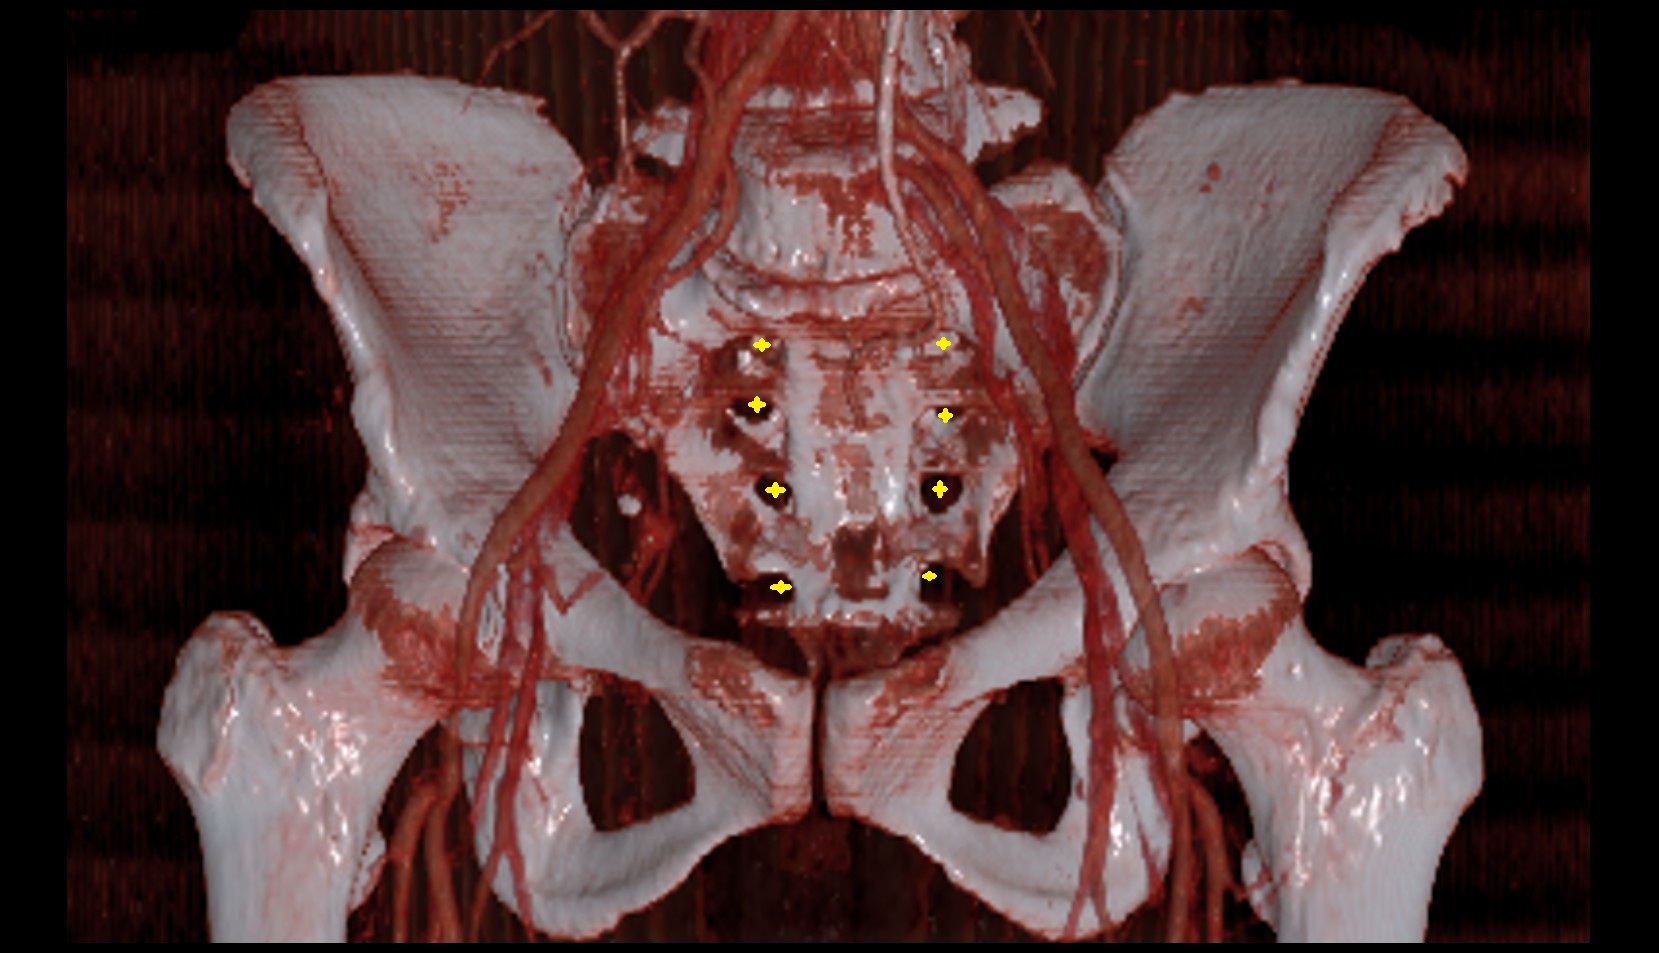

- Sacrum

- Posterior sacral foramina

- Anterior sacral foramina

- Internal iliac artery

- Superior gluteal artery

- External iliac artery

- common iliac artery

- Aortic bifurcation